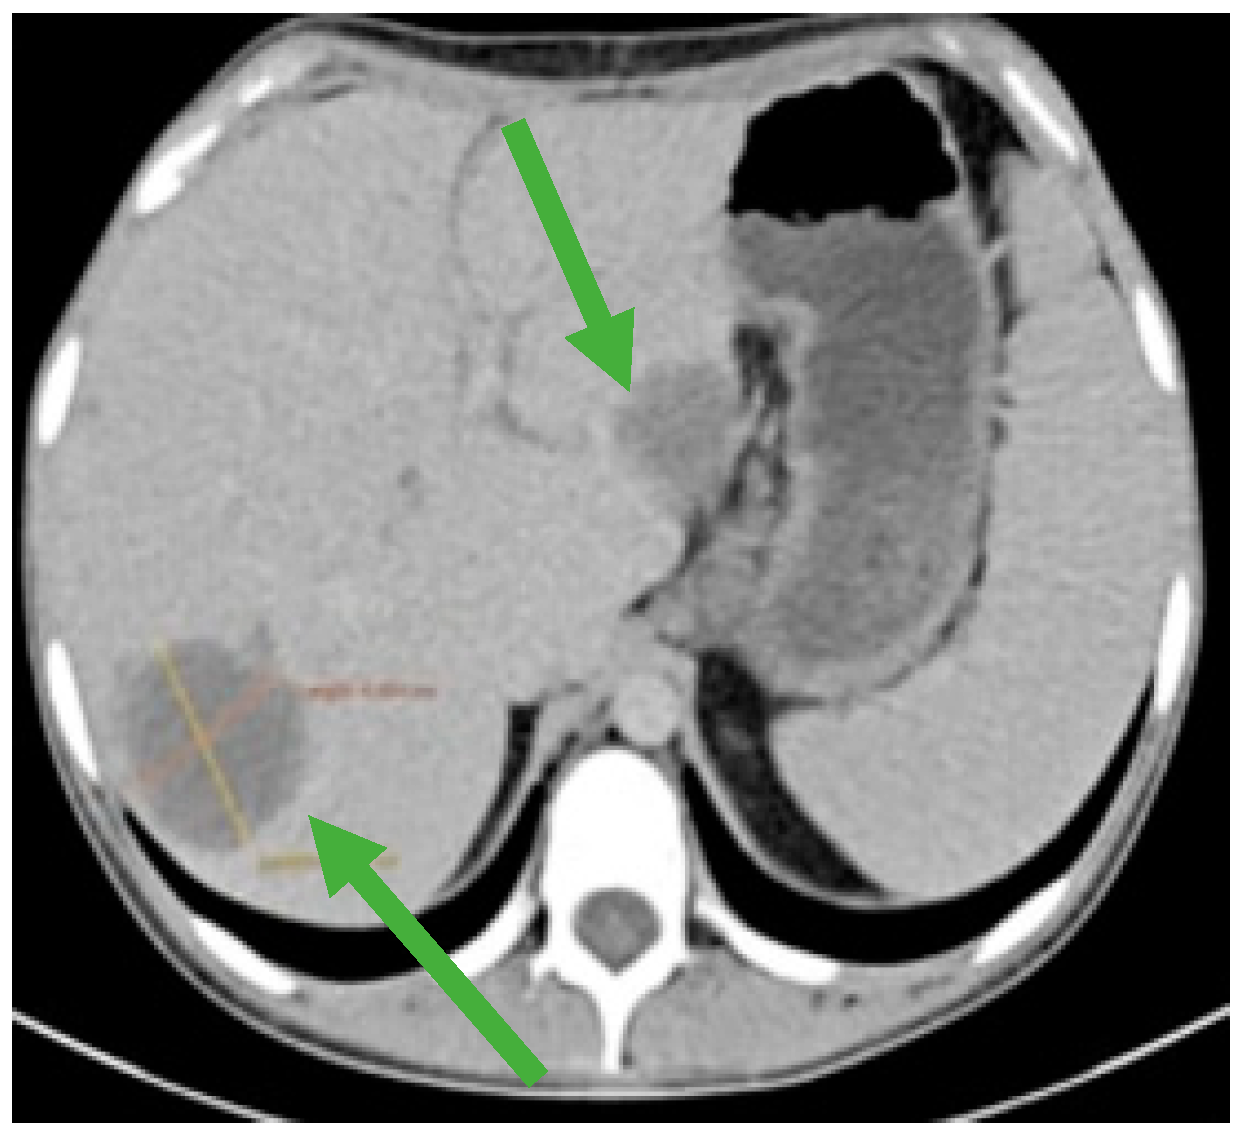

Figure 4.

CT scan showing liver metastases in numerical and dimensional progression (green arrows).